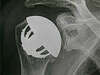

Toutes ces complications peuvent conduire à une nouvelle intervention et au changement éventuel de la prothèse comme le montrent les deux radiographies ci-dessous.

Luxation invétérée non réductible de prothèse (image de gauche). Changement complet de la prothèse au bout de 6 mois. Contrôle radio à un an (image de droite)